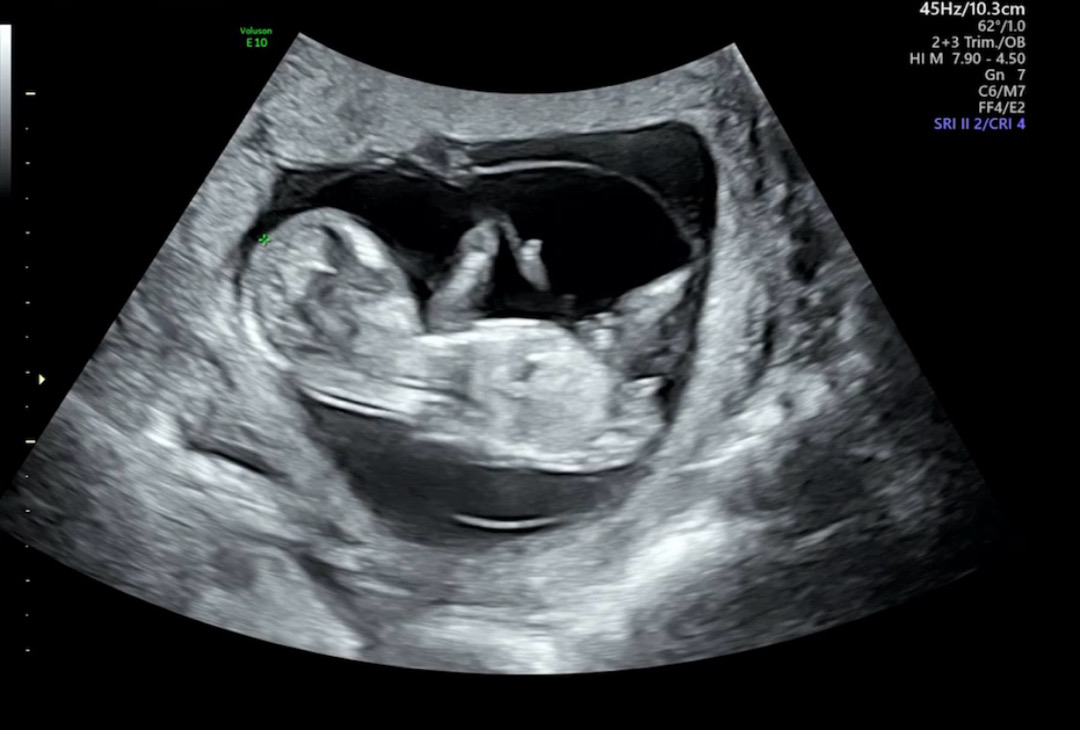

12주3일 성별궁금해요☺

각도법 봐주세요~☺☺

아들 같아요!

딸이용